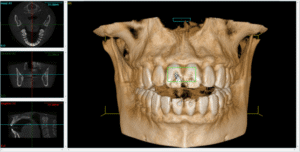

Skipped Diagnostics and Planning

Affordable implant dentistry still requires:

• 3D CBCT imaging

• Bone quality assessment

• Bite and force analysis

Cut-rate clinics often skip steps to move faster. That’s how implants end up placed at the wrong angle or in weak bones.